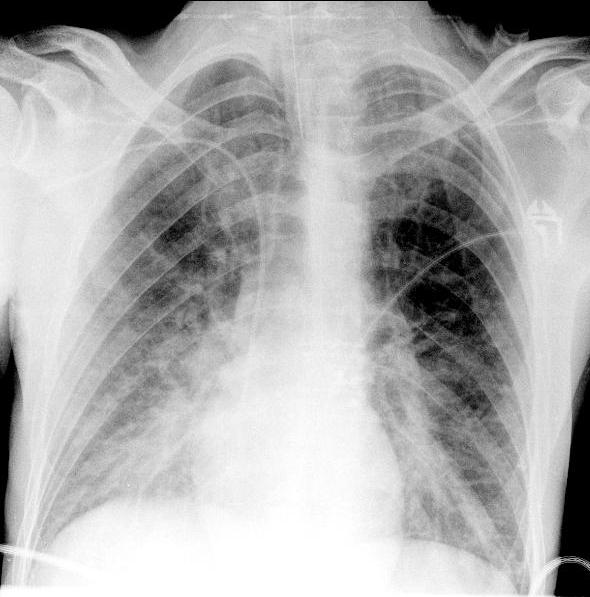

Рис. 2. ЭКГ пациента до операции. Какая-либо патология отсутствует. АД удалось стабилизировать на уровне 120/70 мм рт.ст., ЧСС - 80 уд/мин. Учитывая развитие тяжелого интраоперационного осложнения, операцию решено прекратить, и пациент в состоянии наркозного сна доставлен в отделение реанимации и интенсивной терапии, где была продолжена ИВЛ в режиме синхронизированной перемежающейся принудительной вентиляции (SIMV) - PC, ЧД=12, FiO2=0,4, SpO2=99%. Сохранялась тенденция к гипотонии, требовавшая дополнительной инфузионной терапии коллоидными и кристаллоидными растворами и увеличения дозы норадреналина. На рентгенограмме органов грудной полости (рис. 3) появилось диффузное снижение прозрачности обоих легочных полей по типу «матового стекла».

Рис. 3. Рентгенограмма органов грудной полости в прямой проекции. Тень средостения не смещена. Отмечается выраженное диффузное снижение прозрачности легочной ткани по типу «матового стекла». Выполнена ЭхоКГ, по данным которой отмечалась субтотальная гипокинезия левого желудочка со снижением показателей насосной функции сердца: ФВ 41-42%, СИ=1,8 л/мин·м2. По данным биохимического анализа крови, тропонин 1,06 мкг/л (N<0,1 мкг/л); КФК 166 Ед/л (N<200 Ед/л).